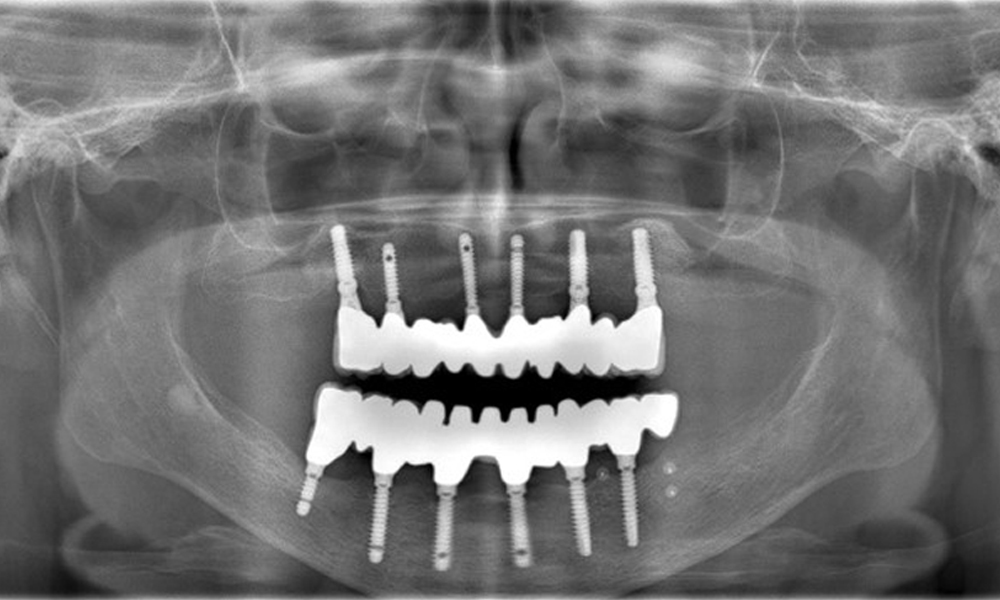

74-годишен пациент се явява за консултация. Анамнезата показва, че пациентът има добре контролирана хипертония и приема Lixiana. Освен това пациентът е имал карцином на бъбрека през 2020 г. Начинът на живот на пациента е без забележки. Няма останали естествени зъби и има шест импланта в горната и долната челюст, на които са поставени коронки или мостове. Текущите данни не показват периимплантатен мукозит или периимплантит, но въпреки това периодично има (незначително) кръвене при имплантите (възстановяванията).

Възстановявания: импланти в области 011, 013, 015, 021, 023, 025, 031, 033, 035, 042, 044, 046

Употребата на Lixiana представлява рисков фактор, поради което рискът от усложнения се счита за умерен. Оралното здраве е стабилно и добро. За ранно откриване на потенциален периимплантит, по време на контролните прегледи трябва да се измерва дълбочината на сондиране (PD). Ако има увеличение на PD при имплантата в сравнение с изходното ниво, съчетано с дифузно кървене, трябва да се продължи с рентгенова диагностика (напр. зъбни рентгенови снимки).

Понастоящем състоянието на периимплантатите е стабилно. Поради сложността на надстройките пациентът има умерен риск от развитие и нисък риск от прогресия на периимплантни заболявания.